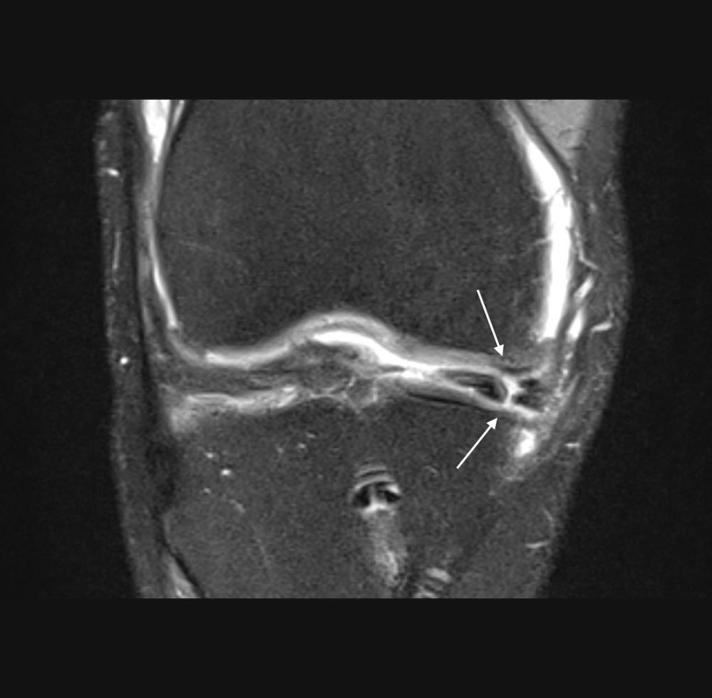

ΑΘΛΗΤΙΚΕΣ ΚΑΚΩΣΕΙΣ:

Αρθροσκόπηση γόνατοςΡήξη μηνίσκουΡήξη χιαστούΑρθροσκόπηση ώμουΡήξη τενοντίου πετάλουΑκρωμιοπλαστικήΑρθροσκόπηση ποδοκνημικήςΑρθροσκόπηση Αγκώνα - Πηχεοκαρπικής

Συγκεκριμένα αναλαμβάνει περιστατικά παθολογίας όπως σκολίωση, αυχενικό σύνδρομο, σπονδυλική στένωση, τενοντίτιδες, αθλητικές κακώσεις, πλατυποδία, άκανθα πτέρνας, οστεοπόρωση κ.α.,χειρουργικές επεμβάσεις όπως διαδερμική χειρουργική, μεταταρσαλγία, βλαισό δάκτυλο, γαμψοδακτυλία, νευρίνωμα Μόρτον, πτώση μεταταρσίων, οστεοαρθρίτιδα, αρθροπλαστική γόνατος, αρθροπλαστική ισχίου, αρθροσκόπηση γόνατος, ρήξη χιαστού, ρήξη μηνίσκου, αρθροσκόπηση ώμου, σύνδρομο καρπιαίου σωλήνα κ.α.